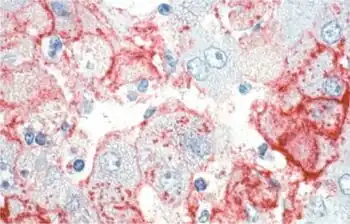

Liver from an individual with Lassa fever

Negative-strand RNA viruses caused many widely known diseases. Many of these are transmitted by arthropods, including the Rift Valley fever virus and the tomato spotted wilt virus.[19][20] Among vertebrates, bats and rodents are common vectors for many viruses, including the Ebola virus and the rabies virus, transmitted by bats and other vertebrates,[21][22] and the Lassa fever virus and hantaviruses, transmitted by rodents.[23][24] Influenza viruses are common among birds and mammals.[25] Human-specific −ssRNA viruses include the measles virus and the mumps virus.[26][27]